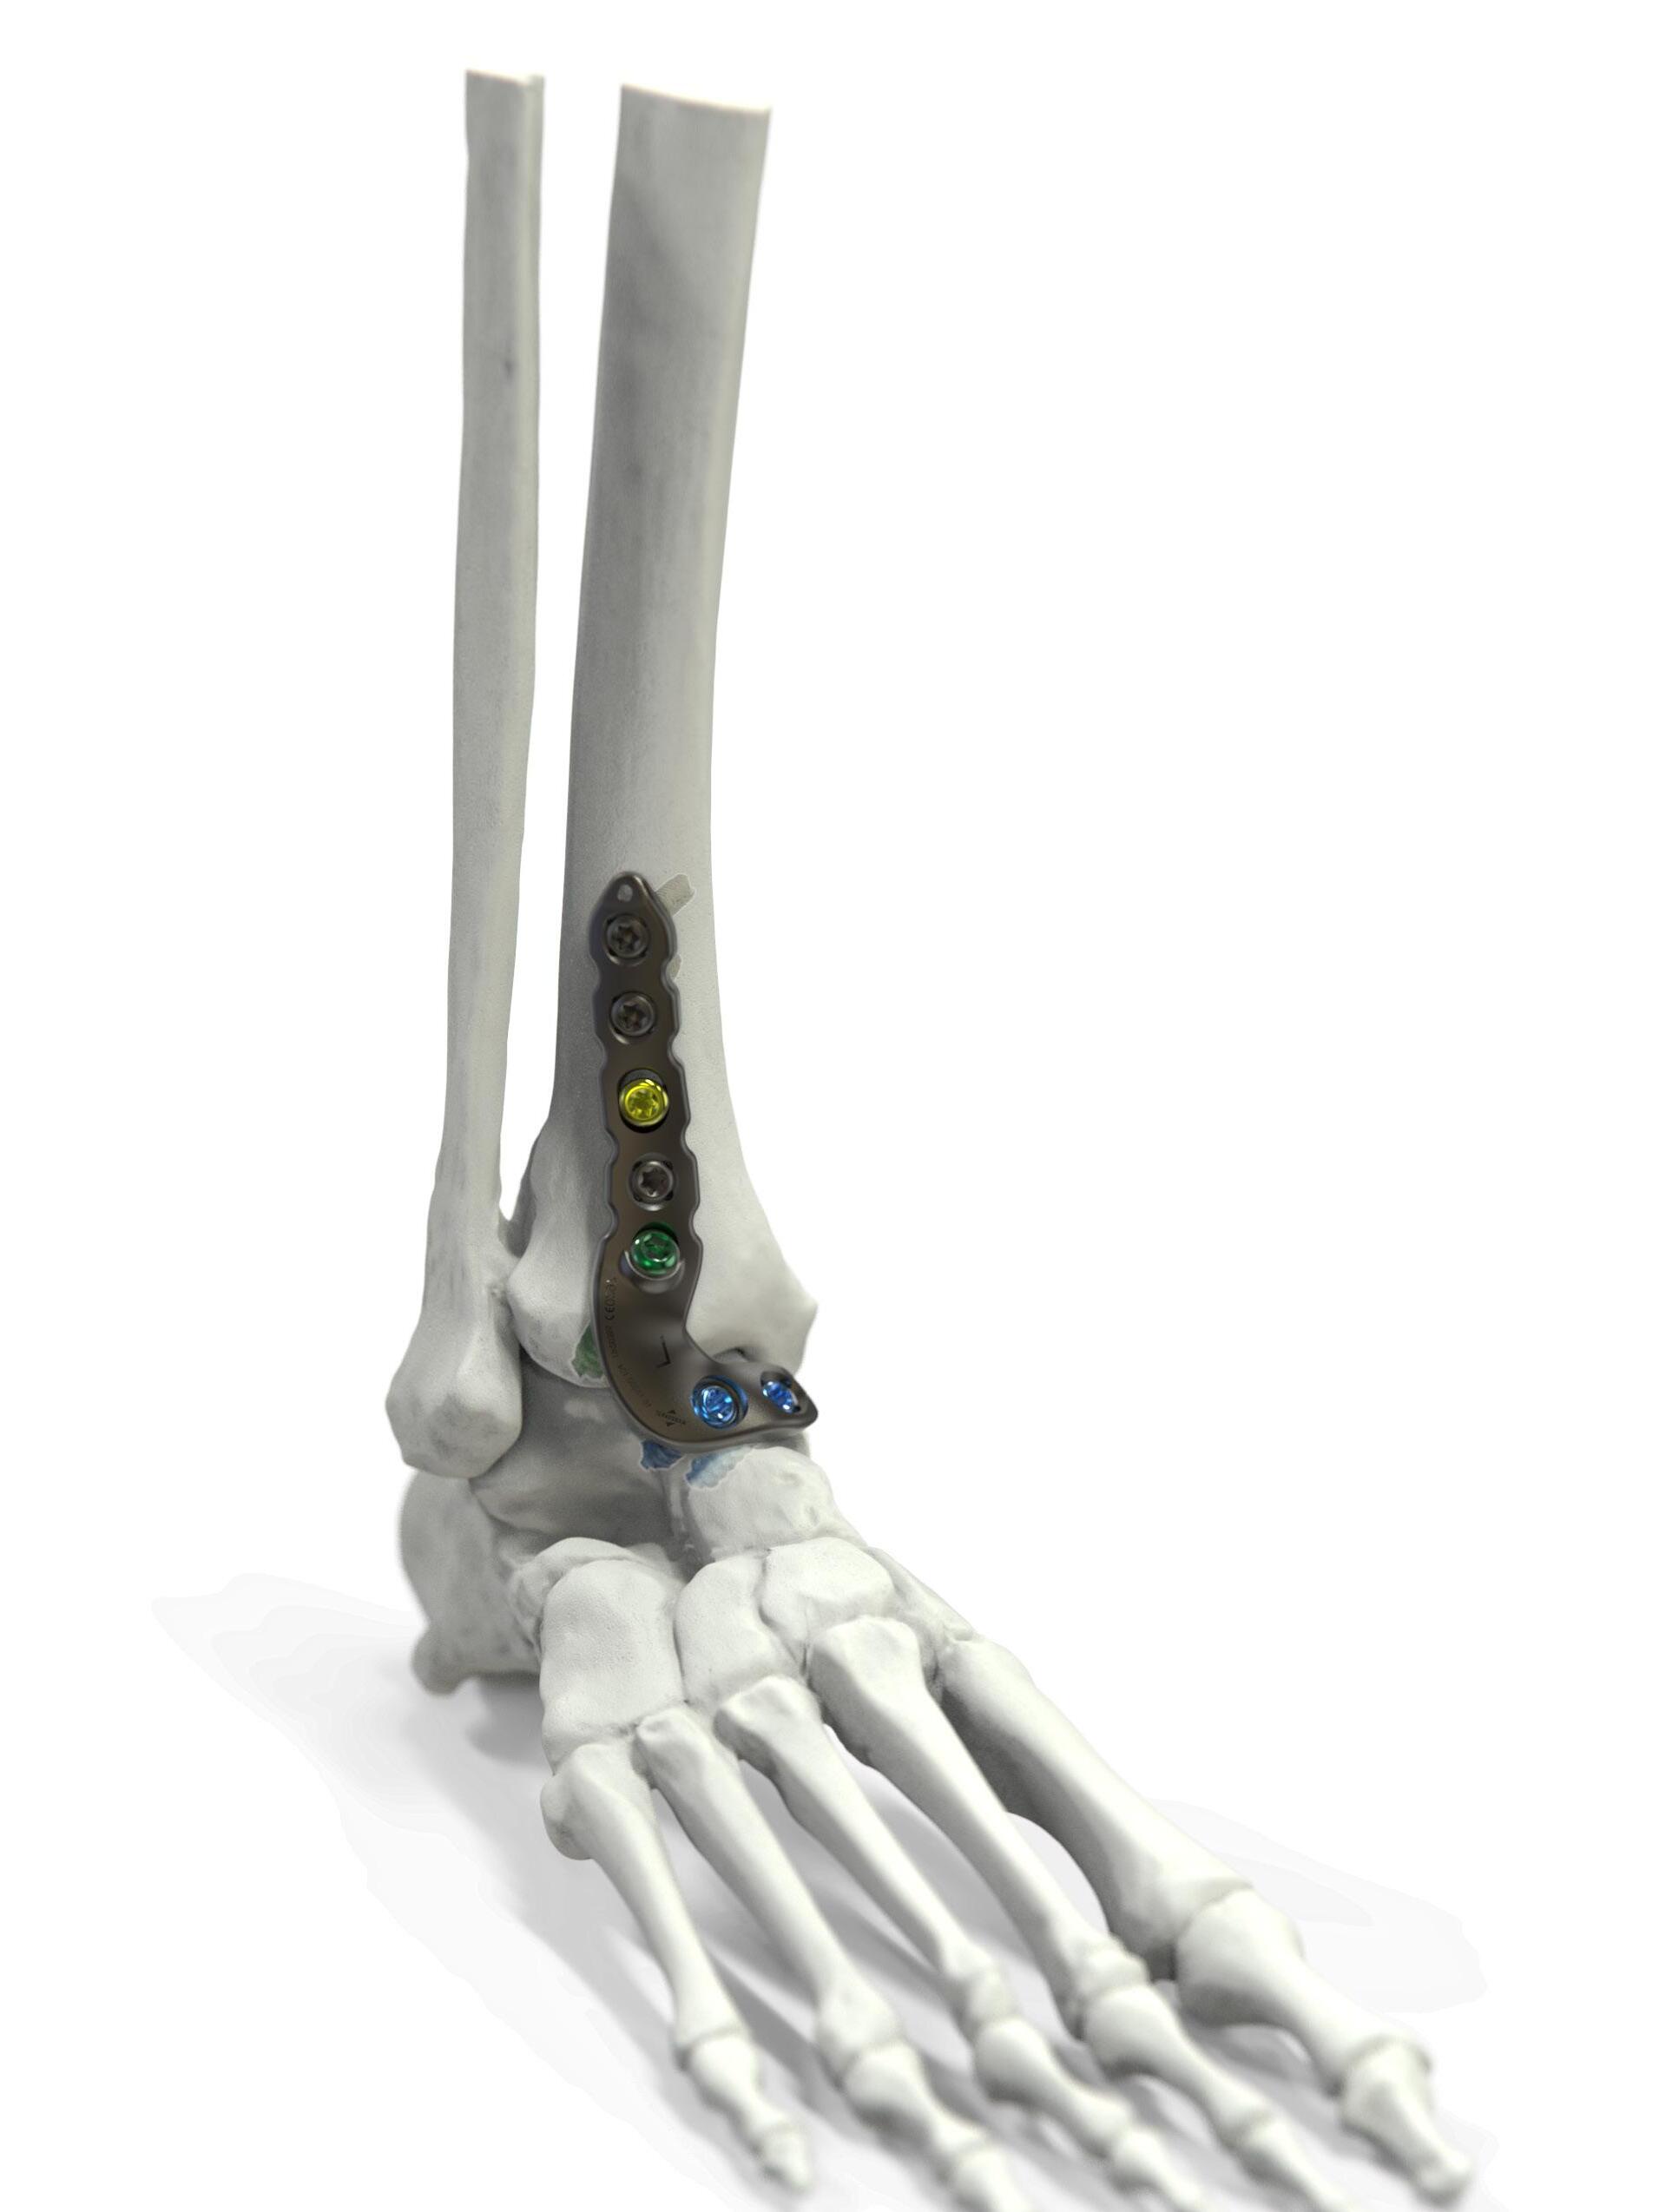

Percutaneous posterolateral malleolus fi xation

Posterior approaches to the ankle are not without morbidity, often causing increased swelling, stiffness and reduction in dorsiflexion due to posterior scar formation compared to direct medial and lateral approaches. Posterior approaches can also limit access to the medial and lateral malleoli and the trajectory of syndesmotic fixation. If posterior metalwork removal is required, approaching this through significant scar tissue can be challenging and causes further stiffness.

Ed Gee Consultant Trauma and Orthopaedics, Salford Royal NHS Foundation Trust

Percutaneous posterior to anterior screw fixation enables a safe method of reduction and stabilisation of the posterolateral fragment without the morbidity of a posterior surgical approach. This then frees the surgeon to perform a more favourable direct lateral approach to the fibula for fixation and syndesmotic stabilisation without having to utilise the posterolateral approach and apply metalwork through the peroneal tendon bed.

Technical aspects of case selection, pre-operative planning, patient position, dissection, reduction,

guidewire placement, screw insertion and radiological checks are all pivotal to perform this safely and effectively.

Mildly displaced posterolateral fragments are selected (Haraguchi 1, Mason 1, 2A and Bartonicek 1, 2). Pre-operative CT is obtained to assess the posterior malleolus fracture and screw trajectory.

The patient is positioned in a lateral position with the injured side up and on an elevating block, placed behind the non-operative leg. This gives a lateral view of the ankle and allows external rotation of the hip to enable mortise view fluoroscopy, access to the anterior ankle for trauma scope and access medially for medial malleolus fixation. Anatomy is marked on the skin using image intensifier and the level of incision is planned to approach the posterior malleolus.

The posterior malleolus should be fixed first to enable proper assessment of joint line and fracture fragment reduction. Once medial and lateral metalwork is in situ this will obscure fluoroscopic assessment of the posterior malleolus. If fibula reduction is required to restore the syndesmosis prior to posterior fixation the fibula can be approached through a direct lateral approach in this position, reduced and held with a clamp or K-wire in a manner that doesn’t obscure fluoroscopic assessment.

A 10mm incision on the lateral edge of the Achilles tendon at the level of the

posterior malleolus and a 10mm tunnel is blunt dissected down to bone using long dissecting scissors. The leg is rotated until the X-ray projection of the posterior malleolus cortex is separate to the posterior cortex of the fibula. A radiolucent depth gauge or 2mm syringe barrel is used as a wire guide to protect the soft tissues. A guidewire is placed on the posterior malleolus cortex by feel and the leg rotated until there is no overlap between cortex and wire to help judge the exact position in relation to the fracture

and to check the wire is on the tibial cortex and not the fibula.

The guidewire is passed into the fragment and the position is checked on the AP image. The fibula is reduced into the incisura with thumb pressure. The leg is then rotated until the fracture plane is visible on fluoroscopy. The depth gauge/ syringe and guidewire are used to joystick the fragment into position and the wire is passed across the fracture. If the fragment requires further inferior translation

the wire can be angled inferiorly so that screw compression will translate the fragment distally. Once the wire is across the fragment, the depth gauge is pushed against the posterior malleolus to check the fragment will compress. Wire position is checked on the mortise view with depth gauge or artery clip against the posterior tibial cortex to assess the exact entry point, ensuring it will not irritate the fibula or syndesmosis.

The near cortex only is drilled, and one unicortical 4mm cannulated partially threaded screw and washer is inserted under image intensifier. As the washer meets the posterior malleolus it should angle to meet the cortical contour of the posterior malleolus, further confirming correct positioning, and the fracture should be seen to compress. If the wire has been angled inferiorly the fragment should reduce more distally by 1mm or so. Final checks are performed, and the percutaneous portal can be closed with skin suture alone. The surgeon is then free to complete necessary fixation of the malleoli and syndesmosis through direct approaches. n